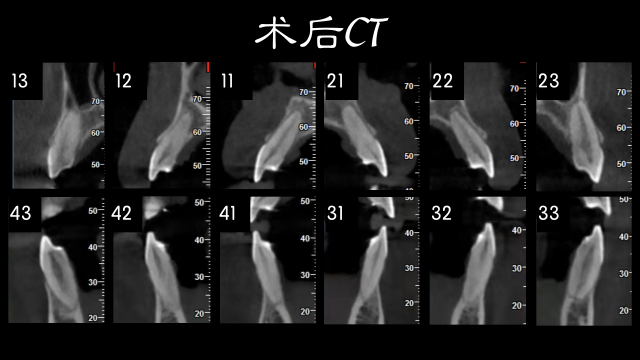

术前检查